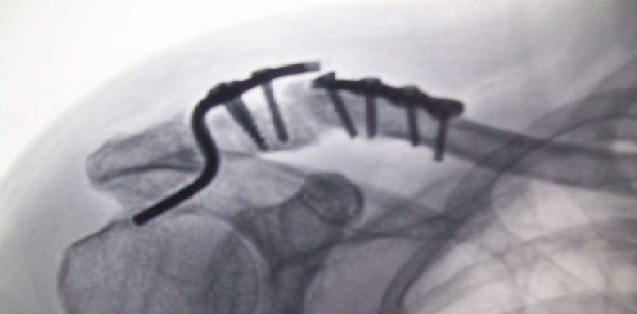

企业应建立有满足出厂检测能力的试验室,并应对产品按批进行出厂检验。特殊检验项目可验证原材料检验报告,但必须通过论证,例如人工关节产品出厂检验要求中的材料可验证原材料检验报告,金属材料铸造可提供每炉质保书或委托检测的报告,锻造件应提供材质报告,铸造件内部的质量应逐件进行X射线检查等。